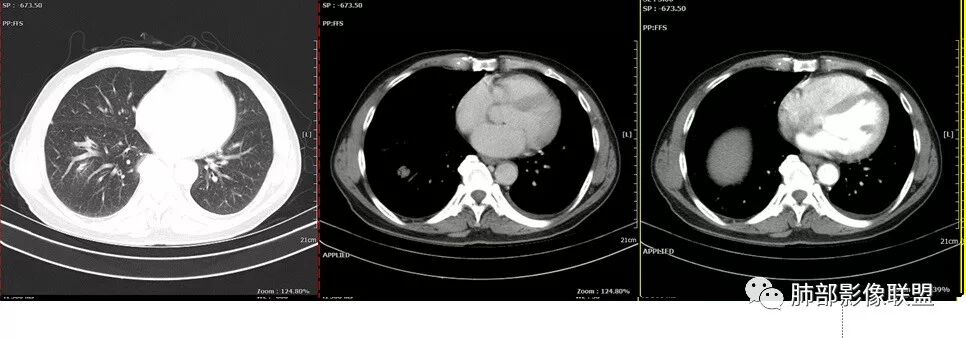

这个是9月7号的平扫CT

右下肺病理没有报癌

但是化疗2次后也缩小了

背段入口在CT上也可以见到了

复查的HRCT

化疗2次。

应该是阻塞性肺炎,抗感染后查PET CT的时候左上肺已经有部分吸收了。

鳞癌起源于支气管粘膜,是气道中最常见的恶性肿瘤,易造成支管壁增厚,并突入腔内形成结节,造成狭窄、阻塞或截断;早期鳞癌表现为沿支气管生长的梭形结节或局限性增厚,辖区内常出现阻塞性炎症,这样的病灶赢多平面重建并仔细观察支气管改变;如果有支气管壁偏心性增厚伴管腔狭窄或腔内结节形成,都要想到早期鳞癌的可能性,复查或内窥镜检查是必要的。

鳞癌好发于中老年人,与吸烟关系密切,如果发现不易吸收的,或同一部位反复无常局限性肺炎,我们应当仔细观察支气管壁的病变除外阻塞的可能;该病例右肺下叶背段及左肺上叶支气管有肿块及管壁的增厚,应当想到恶性可能。